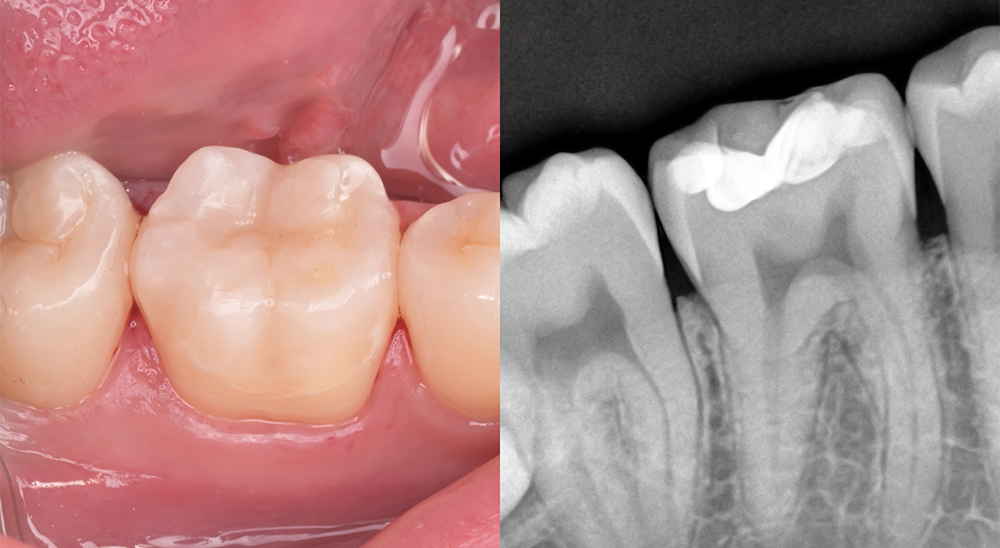

삭제의 핵심은

정밀함에 있습니다

치아를 지키는 치료는

얼마나 정확히 다루느냐의 문제입니다.

연세일등치과는 최대 보존을 단순한 목표가 아닌

정밀한 진단과 설계의 결과물로 봅니다.

건강한 부위와 손상 부위를 면밀히 구분하고,

필요한 만큼만 조심스럽게 다듬어

치아 본연의 구조를 최대한 보존하는 치료를 진행합니다.

레진빌드업, 이러한 가치를 담아 진료합니다

보존 중심 접근 │ 자연치아의 건강한 부분을 가능한 보존하는 것을 목표로 진료 계획을 세웁니다.책임감 있는 진료 │ 상담부터 마무리까지, 모든 과정을 치과의사가 직접 세심하게 진행합니다.정밀 접착 과정 │ 치아와 재료가 긴밀하게 결합될 수 있도록 세심한 접착 단계를 거칩니다.자연스러운 조화 │ 주변 치아와의 색상이나 형태 등 전체적인 조화를 고려하여 수복을 진행합니다.